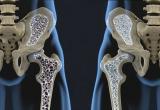

Немецкие врачи рассказали о заболеваемости остеопорозом в молодом возрасте. По случаю Всемирного дня остеопороза эксперты Университетской больницы Дрездена напомнили общественности о том, что остеопороз...